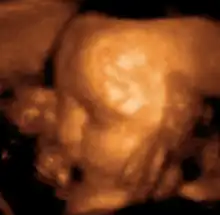

Head of a fetus, aged 29 weeks, in a "3D ultrasound"

The potential for ultrasonic imaging of objects, in which a 3 GHz sound wave could produce resolution comparable to an optical image, was recognized by Sergei Sokolov in 1939. Such frequencies were not possible at the time, and what technology did exist produced relatively low-contrast images with poor sensitivity.[34] Ultrasonic imaging uses frequencies of 2 megahertz and higher; the shorter wavelength allows resolution of small internal details in structures and tissues. The power density is generally less than 1 watt per square centimetre to avoid heating and cavitation effects in the object under examination.[35] Ultrasonic imaging applications include industrial nondestructive testing, quality control and medical uses.[34]

Medical ultrasound is an ultrasound-based diagnostic medical imaging technique used to visualize muscles, tendons, and many internal organs to capture their size, structure and any pathological lesions with real time tomographic images. Ultrasound has been used by radiologists and sonographers to image the human body for at least 50 years and has become a widely used diagnostic tool. The technology is relatively inexpensive and portable, especially when compared with other techniques, such as magnetic resonance imaging (MRI) and computed tomography (CT). Ultrasound is also used to visualize fetuses during routine and emergency prenatal care. Such diagnostic applications used during pregnancy are referred to as obstetric sonography. As currently applied in the medical field, properly performed ultrasound poses no known risks to the patient.[36] Sonography does not use ionizing radiation, and the power levels used for imaging are too low to cause adverse heating or pressure effects in tissue.[37][38] Although the long-term effects due to ultrasound exposure at diagnostic intensity are still unknown,[39] currently most doctors feel that the benefits to patients outweigh the risks.[40] The ALARA (As Low As Reasonably Achievable) principle has been advocated for an ultrasound examination  that is, keeping the scanning time and power settings as low as possible but consistent with diagnostic imaging  and that by that principle nonmedical uses, which by definition are not necessary, are actively discouraged.[41]